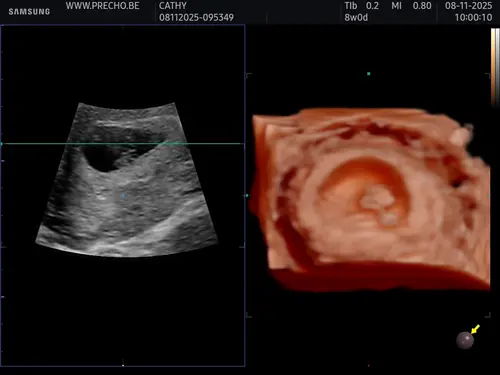

CHATGPT zegt met deze uitwendige echo een meisje, wat denken jullie? Ik heb ...

Ja heel lastig lijkt het maar je moet eigenlijk naar de ligging / locatie van je placenta kijken. Ik denk ook een meisje馃┓